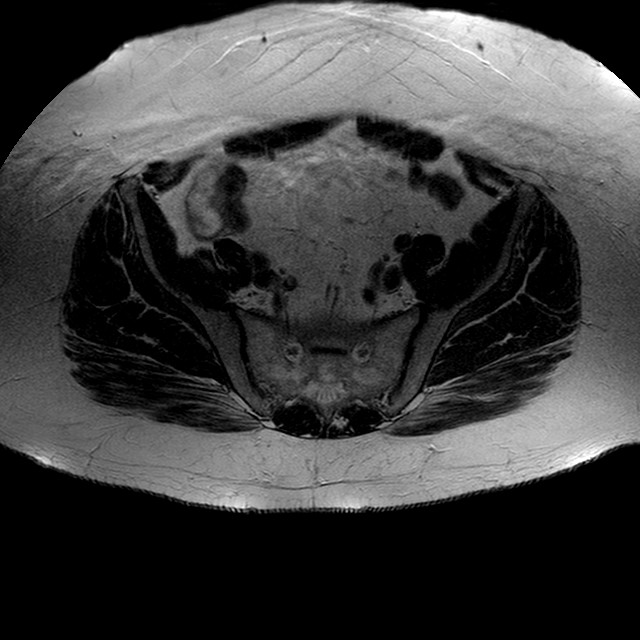

Esami: RMN BACINO

T2w TSE

Evidenti e simmetriche alterazioni osteofitosiche in regione coxo femorale con riduzione delle rime articolari. Degenerazione completa del cercine glenoideo. Non attuali segni di versamento articolare. Non segni di edema osseo che escludono attuale algodistrofia od osteonecrosi. Lieve e simmetrica riduzione del trofismo della muscolatura glutea.